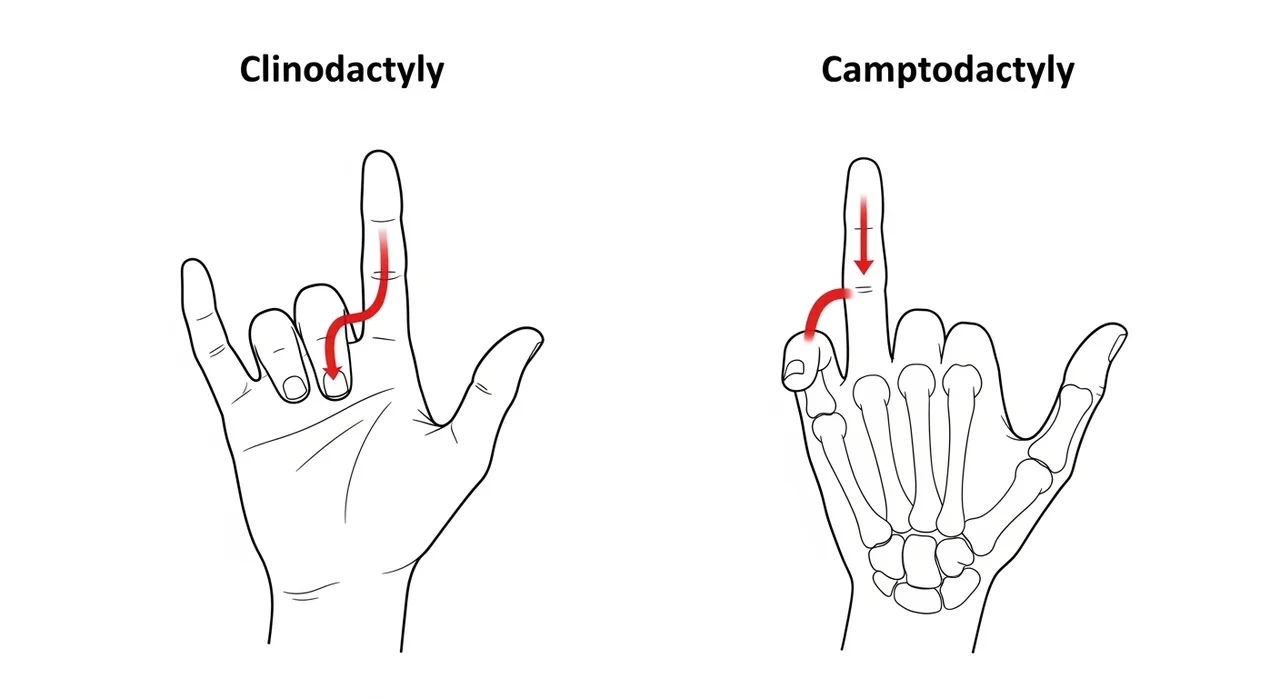

굴지증 vs 측만지증, 무엇이 다른가요?

새끼손가락 휨 증상은 의학적으로 크게 두 가지로 구분됩니다. 자신의 상태가 어디에 해당하는지 확인하는 것이 중요합니다.

| 구분 | 측만지증 (Clinodactyly) | 굴지증 (Camptodactyly) |

|---|---|---|

| 변형 방향 | 옆으로(약지 쪽으로) 휘어짐 | 안으로(손바닥 쪽으로) 굽어짐 |

| 주요 원인 | 중간 마디 뼈의 기형 (삼각형 모양 뼈) | 신전건(펴는 힘줄)의 이상 혹은 피부 부족 |

| 통증 유무 | 대부분 통증 없음 | 심해질 경우 펴지지 않는 기능적 제한 발생 |

측만지증은 주로 미용상의 문제로 여겨지지만, 굴지증은 손가락을 완전히 펴지 못하는 기능적 문제가 동반될 수 있어 정밀 진단이 필요합니다.